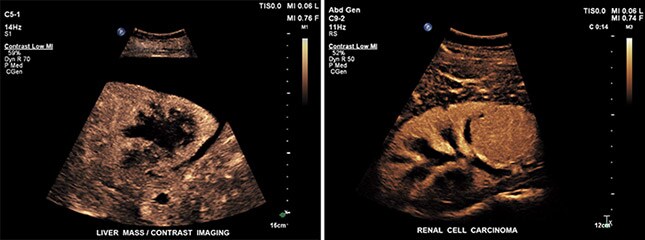

Contrast image of liver mass (left) and renal cell carcinoma (right)